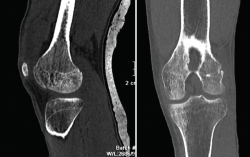

En la osteocondritis se aprecia una lesión subcondral caracterizada por resorción ósea, colapso y la formación de un secuestro.

El estudio por RM es una herramienta valiosa para diagnosticar e identificar las lesiones del cartílago. Conocer el aspecto del cartílago y saber cuánto y cuándo se lesiona, basándose en las clasificaciones actuales, permiten al radiólogo proporcionar la máxima información al clínico(20).

Figura 53. Corte de secuencia sagital (A) y axial (B) T2 Fat-Sat de RM de rodilla: lesiones osteocondrales en el fémur y la rótula.

Numerosos estudios demuestran la utilidad de la RM para definir la estabilidad o inestabilidad de la lesión en la osteocondritis, destacando su carácter no invasivo y la capacidad de valorar la progresión y la respuesta al tratamiento(21)(Figuras 53 y 54).

Figura 54. Corte de secuencia T1 y T2 Fat-Sat coronal de resonancia magnética: gran osteocondritis en el cóndilo femoral interno con edema en la medular adyacente.